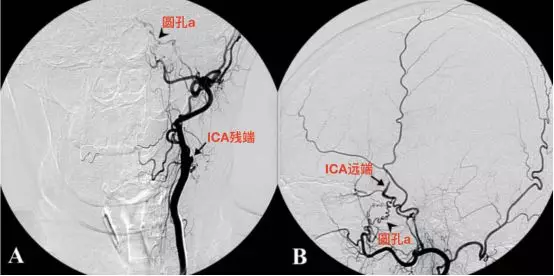

Nam等报道一例60余岁的女性病人,因面肌痉挛入院。造影发现颈内动脉颈段闭塞,通过圆孔动脉重建了颈内动脉颅内段血流。

A,左侧颈总动脉造影,正位,显示左侧颈内动脉起始段闭塞,可见圆孔动脉(箭头)。B,圆孔动脉增粗,走行迂曲,与颈内动脉海绵窦段下外侧干吻合建立侧支循环。